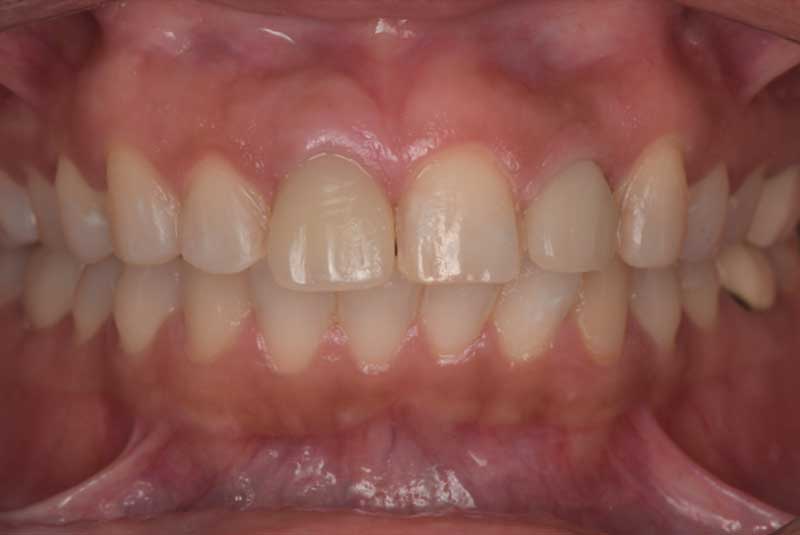

Porcelain Fused Zirconia implant crowns for Maxilla and Mandible, Veneers Before & After